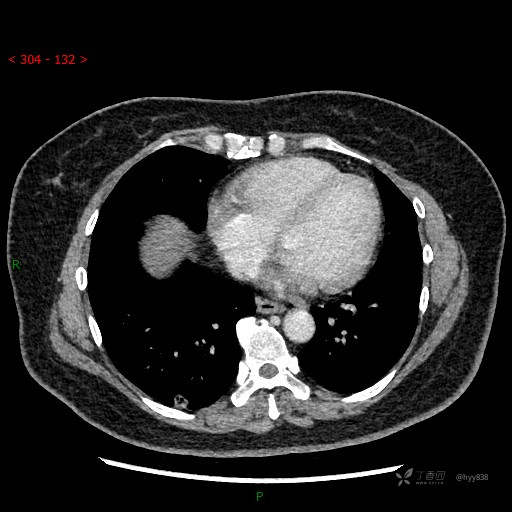

51岁/F,体检发现肺结节,又见“鬼脸”,增强也有特点,请分析---结果公布~

简要病史:体检发现右下肺结节,来我院行进一步增强检查并手术

胸部CT平扫

胸部CT增强--动脉期

静脉期